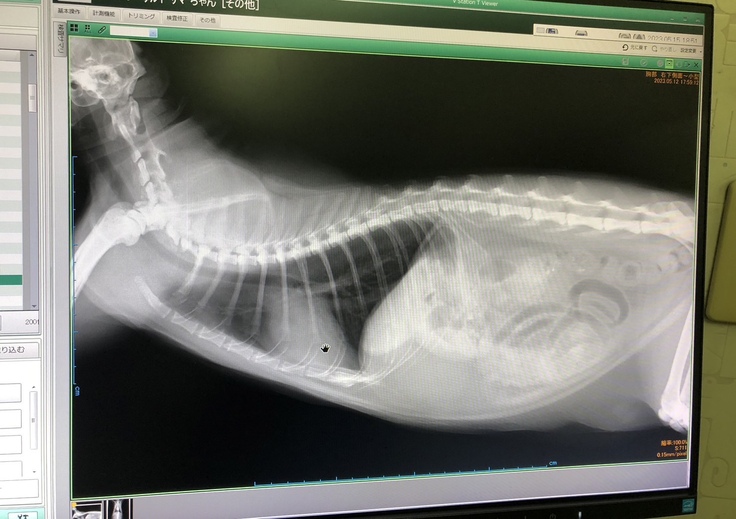

とらちゃんの元に駆けつけると、現場に居合わせた方からなんと「とらちゃんの里親を検討したい」とのお申し出が!仕事で訪れている方で、以前からとらちゃんを見かけていて気になっていたとのこと。こんな奇跡のような出会いと同時に、とらちゃんは地元の動物病院にて闘病生活に入ったのでした。

(ぐったりしているとらちゃん)

「結論から言うと重症で、この2週間が山場。 貧血、黄疸の数値が悪く、ヘモプラズマ感染症と思われるが、免疫介在性溶血性貧血(IMHA)や伝染性猫腹膜炎(FIP)の可能性もあり、後者2つだと非常に深刻。明日エコー検査や内臓系の出血などを調べ、輸血と免疫抑制の薬を使う判断をする。猫エイズ・猫白血病はどちらも陰性」

(搬送後、酸素室に入ったとらちゃん)

「ヘモプラズマかどうか、より正確な診断を下すには外部の検査機関に血液検査を依頼する必要がある。費用は13,000円。貧血は横這いで悪くはなってはいない。次の目標は横這い状態を脱して上昇すること。黄疸は下がっている。今週、エコ―検査をして出血が見当たらなければIMHAの可能性が高い。血液型はA型。相変わらず食べる量は少ないが、美味しいものは食べる。引き続き酸素室で治療を受けているが、入院時より幾分元気になった様子。」

「採血の時、抵抗するようになった。給餌の時にシャーシャー言っている。昨日の晩ご飯は完食。ウンチはまだ出ていない。炎症を抑えるためステロイドを投与、免疫抑制剤の服用も始まっている。エコー検査結果は、出血無し、腹水・胸水無し、肝臓・脾臓がちょっと大きくなっているとのこと(免疫の病気は腫れやすい)。心臓も問題無し。IMHAの可能性がある場合、半年くらい『シクラバンス』という薬を投与する必要がある。費用は同院の野良猫割引を利用しても1カ月8,000円ほど」

「今、すい臓の炎症を抑える注射をしている。すい臓の数値は正常だが、少し腫れているので胆汁の流れが悪くなっている。黄疸が改善すれば退院できる。血球は入院時の13.0と比べると17.4とだいぶ改善。食欲はむらがある。今日現在までの治療費概算は128,590円。ちょうど朝ご飯の時間に遭遇したが、食べっぷりは悪くない様子。昨晩より元気そうで少し安心」

「血球: 16.6黄疸: 0.2値が下がった。SAA: 正常値。膵炎は合併症として出る可能性がある。症状は軽度であり、食欲が出ているので問題なし。当院としてはFIPよりIMHAの可能性が高いと見ている」

(診断書)

(これまでの治療費)

(検査項目)

(血液検査推移 [黄疸:TBIL、血球血中濃度:PCV])